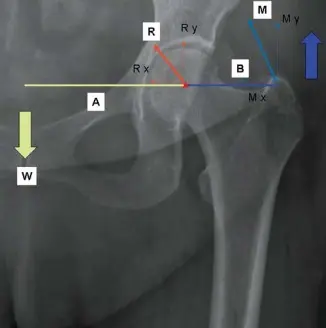

تخيل رافعة: كلما كان ذراع الرافعة أطول للعضلات المبعدة، كلما قل الجهد المطلوب منها لتحقيق التوازن. في مفصل الورك، ذراع الرافعة بين مركز رأس الفخذ والعضلات المبعدة يكون عادةً أقصر من ذراع الرافعة بين مركز رأس الفخذ ووزن الجسم. هذا يضع العضلات المبعدة في وضع ميكانيكي غير مواتٍ، مما يعني أنها يجب أن تولد قوة أكبر من وزن الجسم للحفاظ على استواء الحوض ومنع ما يسمى بـ "مشية ترندلينبرغ" (Trendelenburg lurch)، وهي مشية مميزة تحدث بسبب ضعف عضلات الورك.

شكل 5.1: يعمل مفصل الورك (النجمة الحمراء) بفعالية كنقطة ارتكاز بين وزن الجسم (W) والعضلات المبعدة للورك المعاكسة (M). ذراع الرافعة بين مركز رأس الفخذ والعضلات المبعدة (B) أقل من ذراع الرافعة بين مركز رأس الفخذ ووزن الجسم (A)، مما يضع العضلات المبعدة في وضع ميكانيكي غير مواتٍ. R يمثل قوة رد الفعل الناتجة عن المفصل. "x" و "y" يمثلان المتجهات المقابلة للقوى في الاتجاهين الأفقي والعمودي.